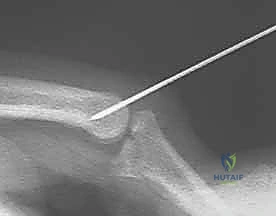

* K-wire Insertion Angle: Insert the K-wire percutaneously, aiming in a retrograde direction, approximately 30 degrees off the long axis of the proximal phalanx. The angle is crucial to ensure the pin is within the bone and not crossing the joint.

* Fluoroscopic Guidance (Constant Monitoring):

* Initial Entry: Advance the K-wire slowly with a power drill or by hand. Confirm its entry into the bone of the proximal phalanx on both AP and lateral fluoroscopic views.

* Guidance through Shaft: Guide the wire through the shaft of the proximal phalanx, aiming slightly volar.

* Target Depth: Advance the K-wire until its tip lies just proximal to the articular cartilage of the proximal phalanx head. The tip should not enter the joint space. This is your blocking point.

Image

Fluoroscopic view of K-wire in proximal phalanx (AP).

Fluoroscopic view of K-wire in proximal phalanx (Lateral).

Fluoroscopic view of K-wire in proximal phalanx, demonstrating blocking position.